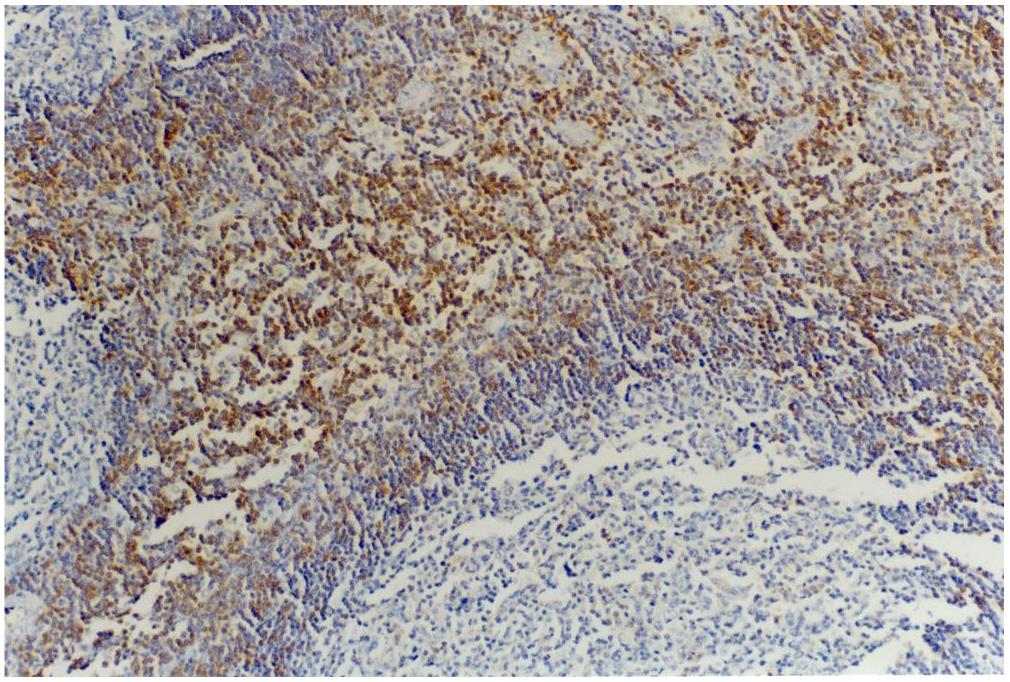

Immunohistochemistry staining of tonsil (paraffin-embedded sections) with anti-CD45RB (MEM-55).